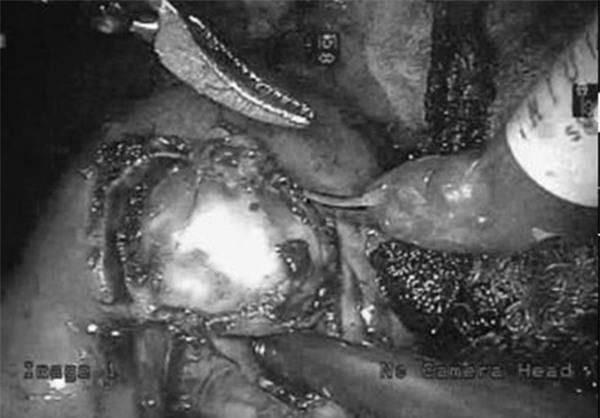

Dùng robot cắt một phần thận cho bệnh nhân.

"Bệnh viện Bình Dân đã triển khai phẫu thuật nội soi cắt một phần thận từ năm 2004. Đến nay, kỹ thuật này cho thấy hiệu quả, an toàn cho người bệnh. Việc sử dụng chất chỉ thị ICG-Fluorescence trong quá trình phẫu thuật giúp các bác sĩ xác định mạch máu nuôi bướu, các hạch di căn để triệt để lấy trọn khối bướu và nạo hạch, đồng thời bảo tồn tối đa phần chủ mô thận lành. Nhờ vậy, tiên lượng sống còn của người bệnh được cải thiện và tỷ lệ tái phát được giảm thiểu đáng kể" – BS Phát cung cấp.